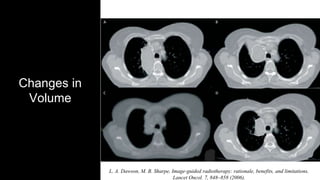

Changes in

Volume

L. A. Dawson, M. B. Sharpe, Image-guided radiotherapy: rationale, benefits, and limitations.

Lancet Oncol. 7, 848–858 (2006).

Changes in Volume K. R.Britton et al., Assessment of Gross Tumor Volume Regression and Motion Changes During Radiotherapy for Non–Small-Cell Lung Cancer as Measured by Four- Dimensional Computed Tomography. International Journal of Radiation Oncology*Biology*Physics. 68, 1036–1046 (2007).

Changes in Volume L. A.Dawson, M. B. Sharpe, Image-guided radiotherapy: rationale, benefits, and limitations. Lancet Oncol. 7, 848–858 (2006).

• #16 This image shows a series of images taken for a given patient at different stages of the therapy and shows the dramatic shape and volume changes that can happen during the course of radiotherapy.